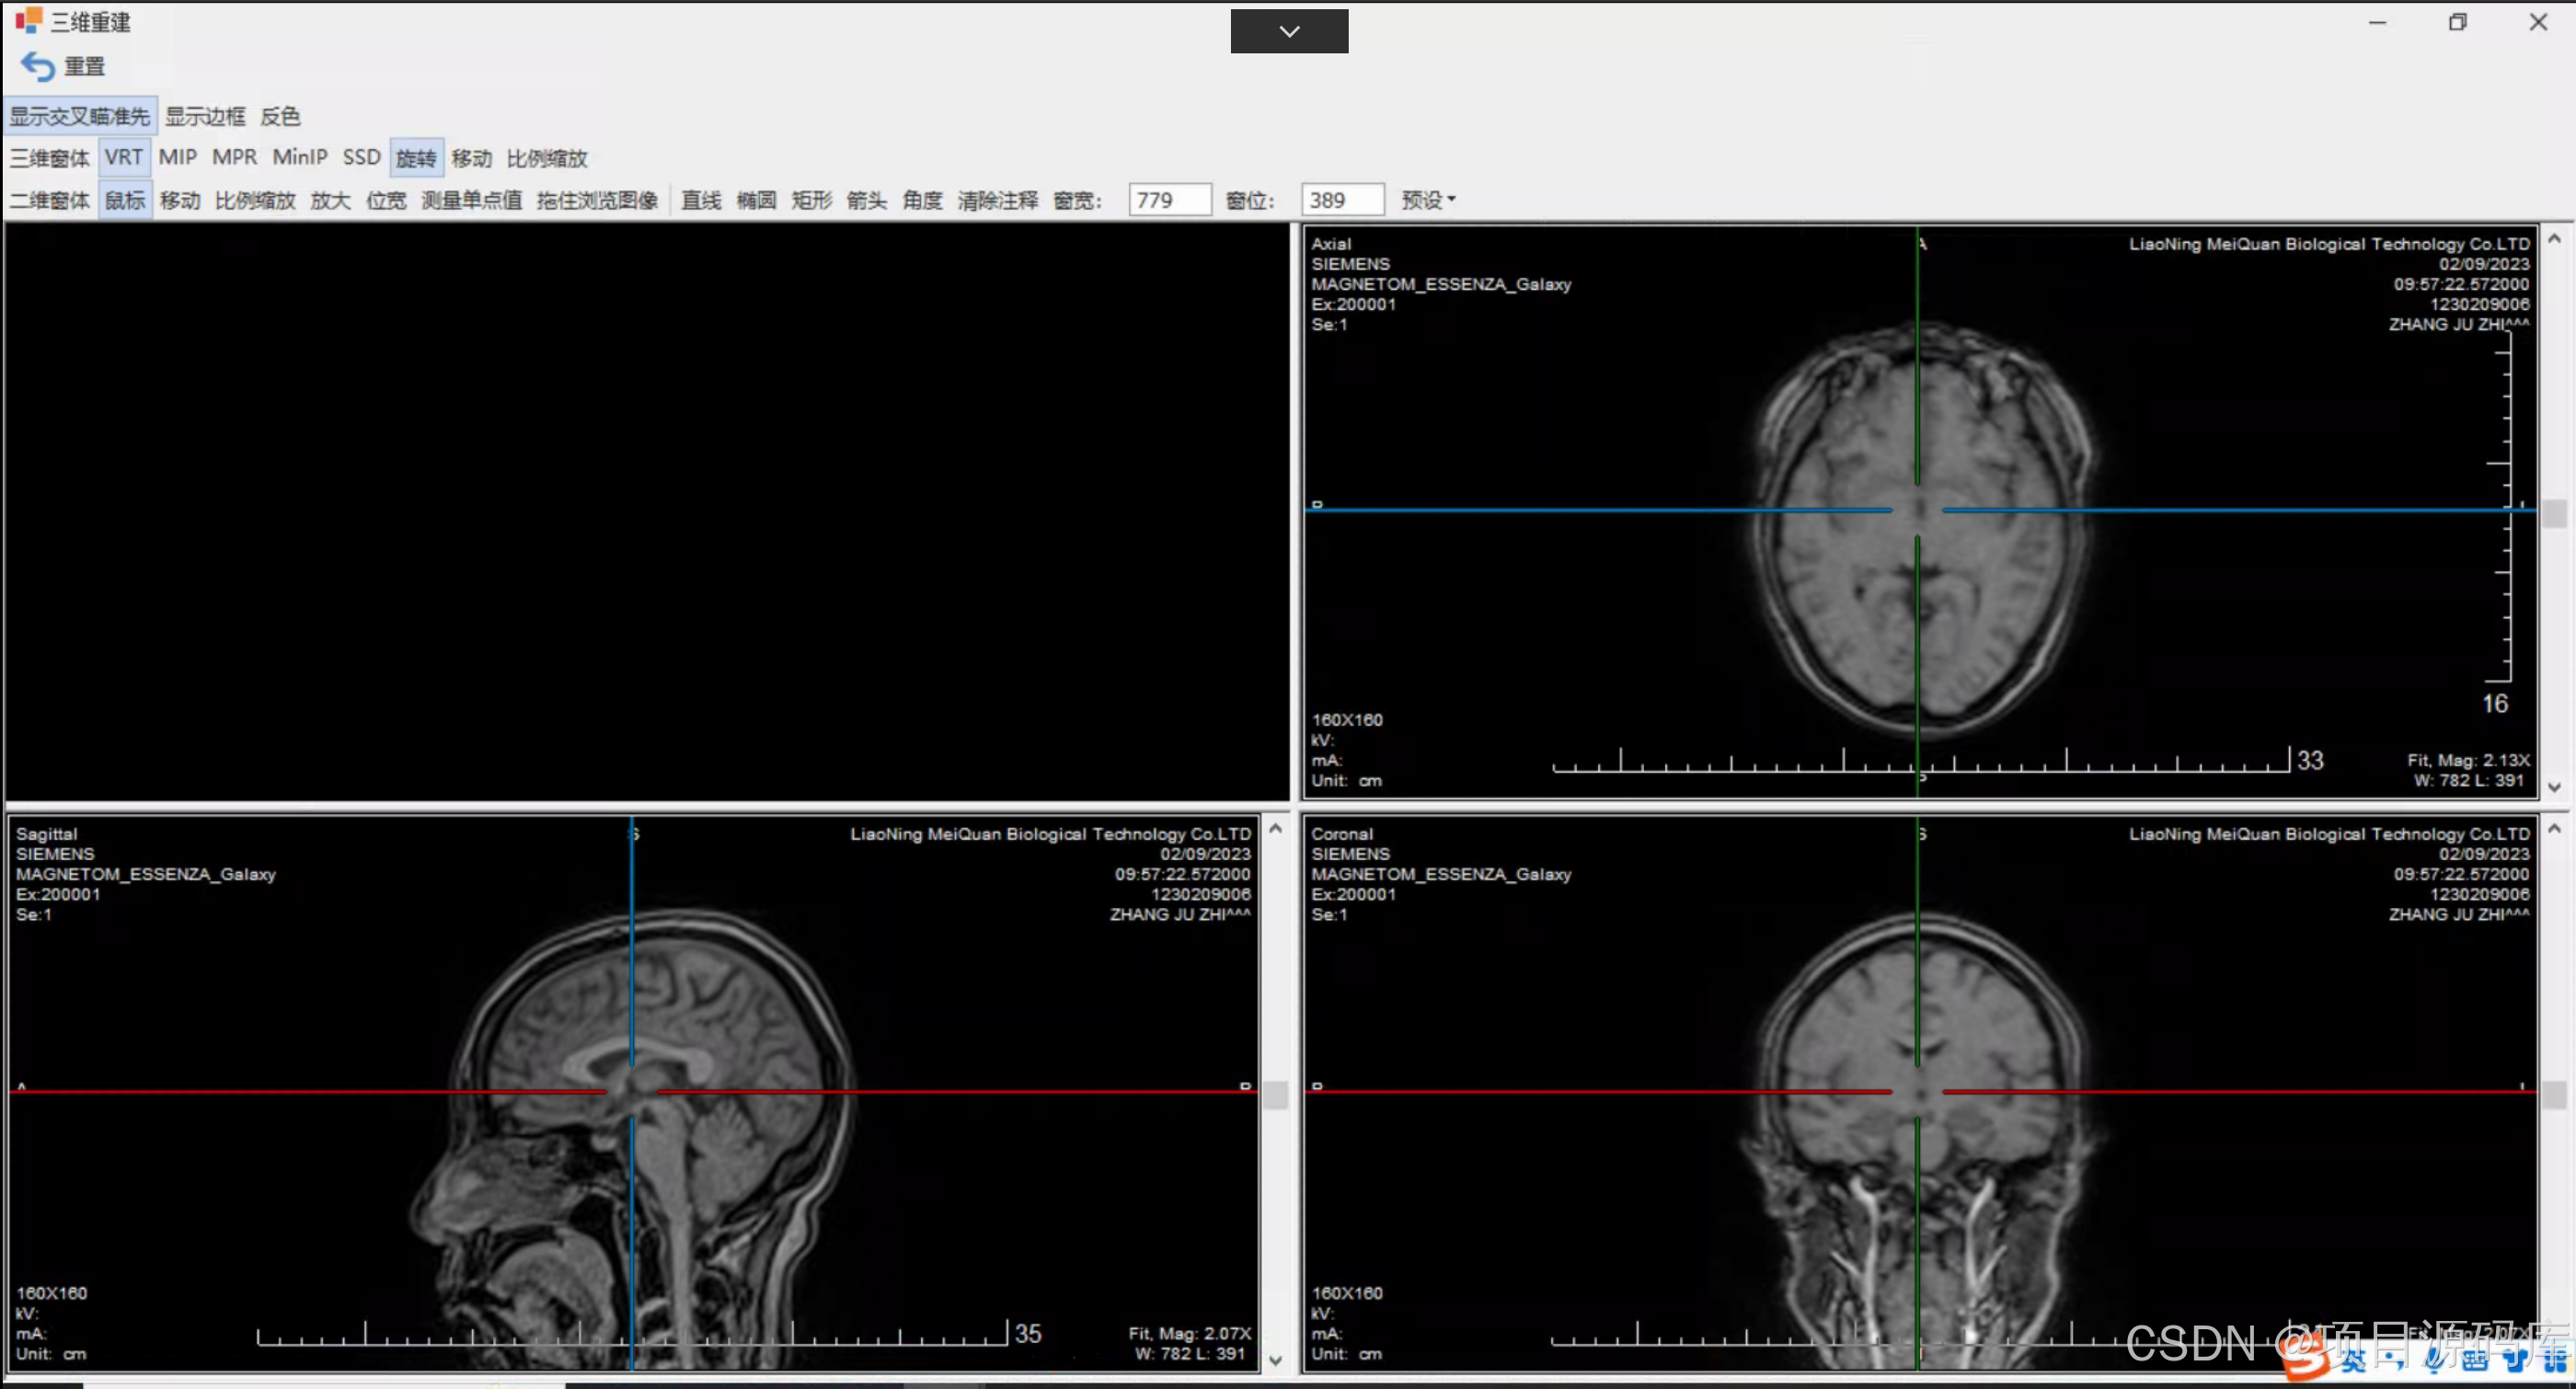

三维重建后处理

CT三维重建技术是指经过计算机软件处理,将连续横断层扫描所收集的信息重建为直观的三维立体图像的一种影像学技术,是图像处理技术的一次重大飞跃。更便于医生诊断病灶。

PACS系统支持3D阅片的原理

PACS系统支持3D阅片的原理基于从一系列二维医学影像(如CT或MRI扫描的切片)中重建三维模型的技术。以下是实现这一功能的关键步骤和技术要点:

数据获取:首先,从PACS系统中导出原始的二维医学影像数据,这些数据通常是DICOM格式,包含了详细的患者信息和图像数据。

图像预处理:对原始图像进行噪声过滤、对比度增强等处理,以提高重建质量。这一步骤是确保后续三维重建准确性的基础。

图像配准:由于不同时间或角度获取的图像可能有微小的位移,需要通过配准算法将这些图像精确对齐,确保重建的三维模型连续且一致。

后处理与分析:重建后的3D模型可以进一步进行旋转、缩放、切割等操作,以不同视角观察,辅助医生进行更深入的分析和诊断。

可视化与交互:通过高性能图形处理器(GPU),PACS系统能够实时渲染3D图像,医生可以通过鼠标或触摸屏进行交互,动态调整视图,从而获得更直观的解剖结构理解。

通过这些技术,PACS系统不仅存储和管理二维医学影像,还能提供强大的3D阅片功能,帮助医生进行更精确的诊断和治疗规划。